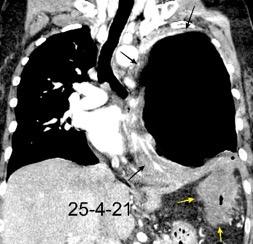

Tromboembolismo pulmonar.

Frecuencia del derrame:

Rx: 32%. TC: 47%

Unilateral. 85%

< 1/3 del hemitórax: 90%

Todos exudados

58% con eritrocitos

21% tabicación lo que causa demora en el diagnóstico

TEP. Empiema pleural. Atelectasia redonda

Porcel JM et al. Analysis of pleural effusions in acute pulmonary embolism: radiological and pleural fluid data from 230 patients. Respirology 2007/ Iguchi T et al. Desquamation of the subpleural lung parenchyma caused by empyema after pulmonary embolism: A case report. Respirol Case Rep. 2022 .